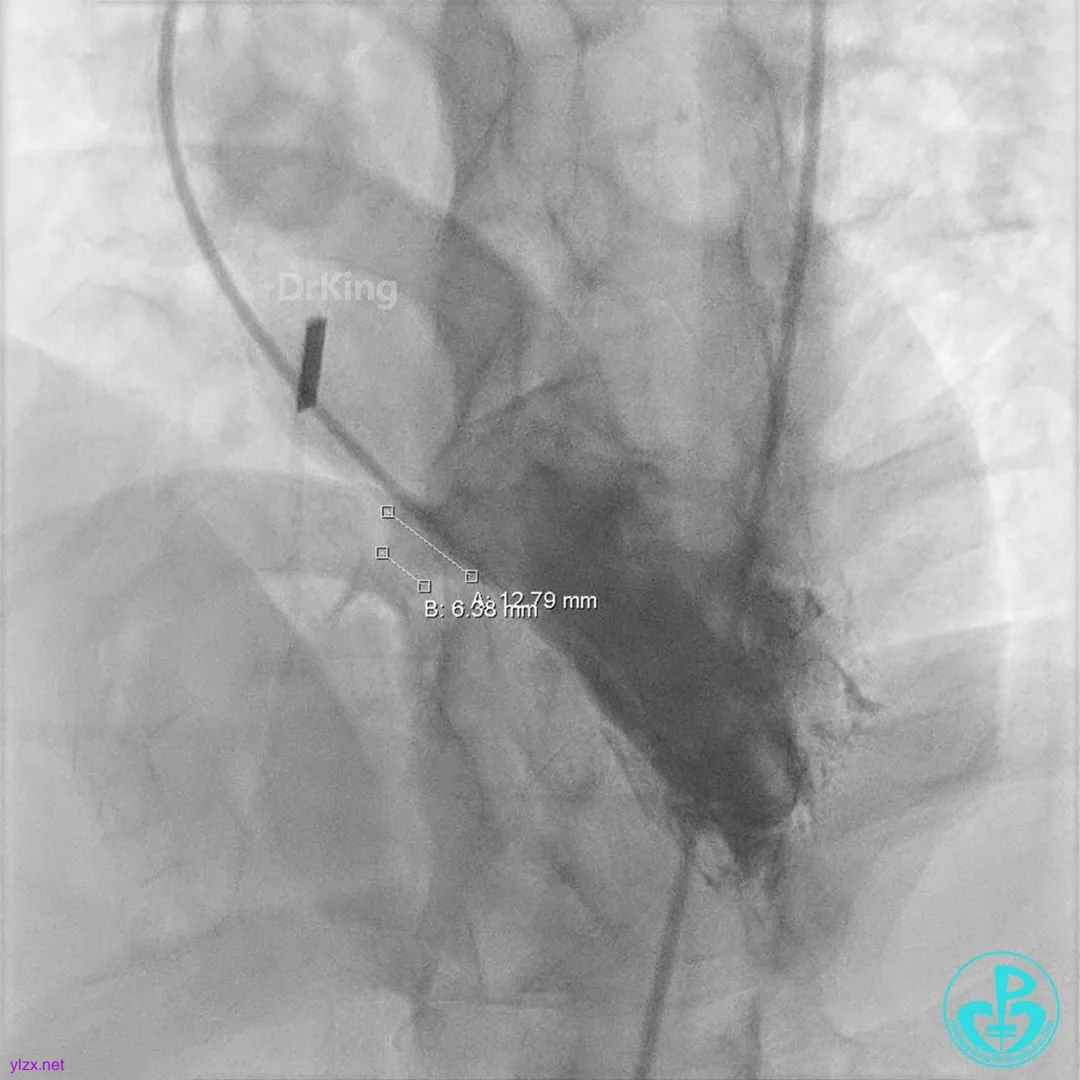

术中造影

结合实际术中造影,为大型膜部瘤室间隔缺损,左室入口直径12.79mm,右室出口直径为6.38mm,选择腰部直径为14的全降解封堵器进行封堵。